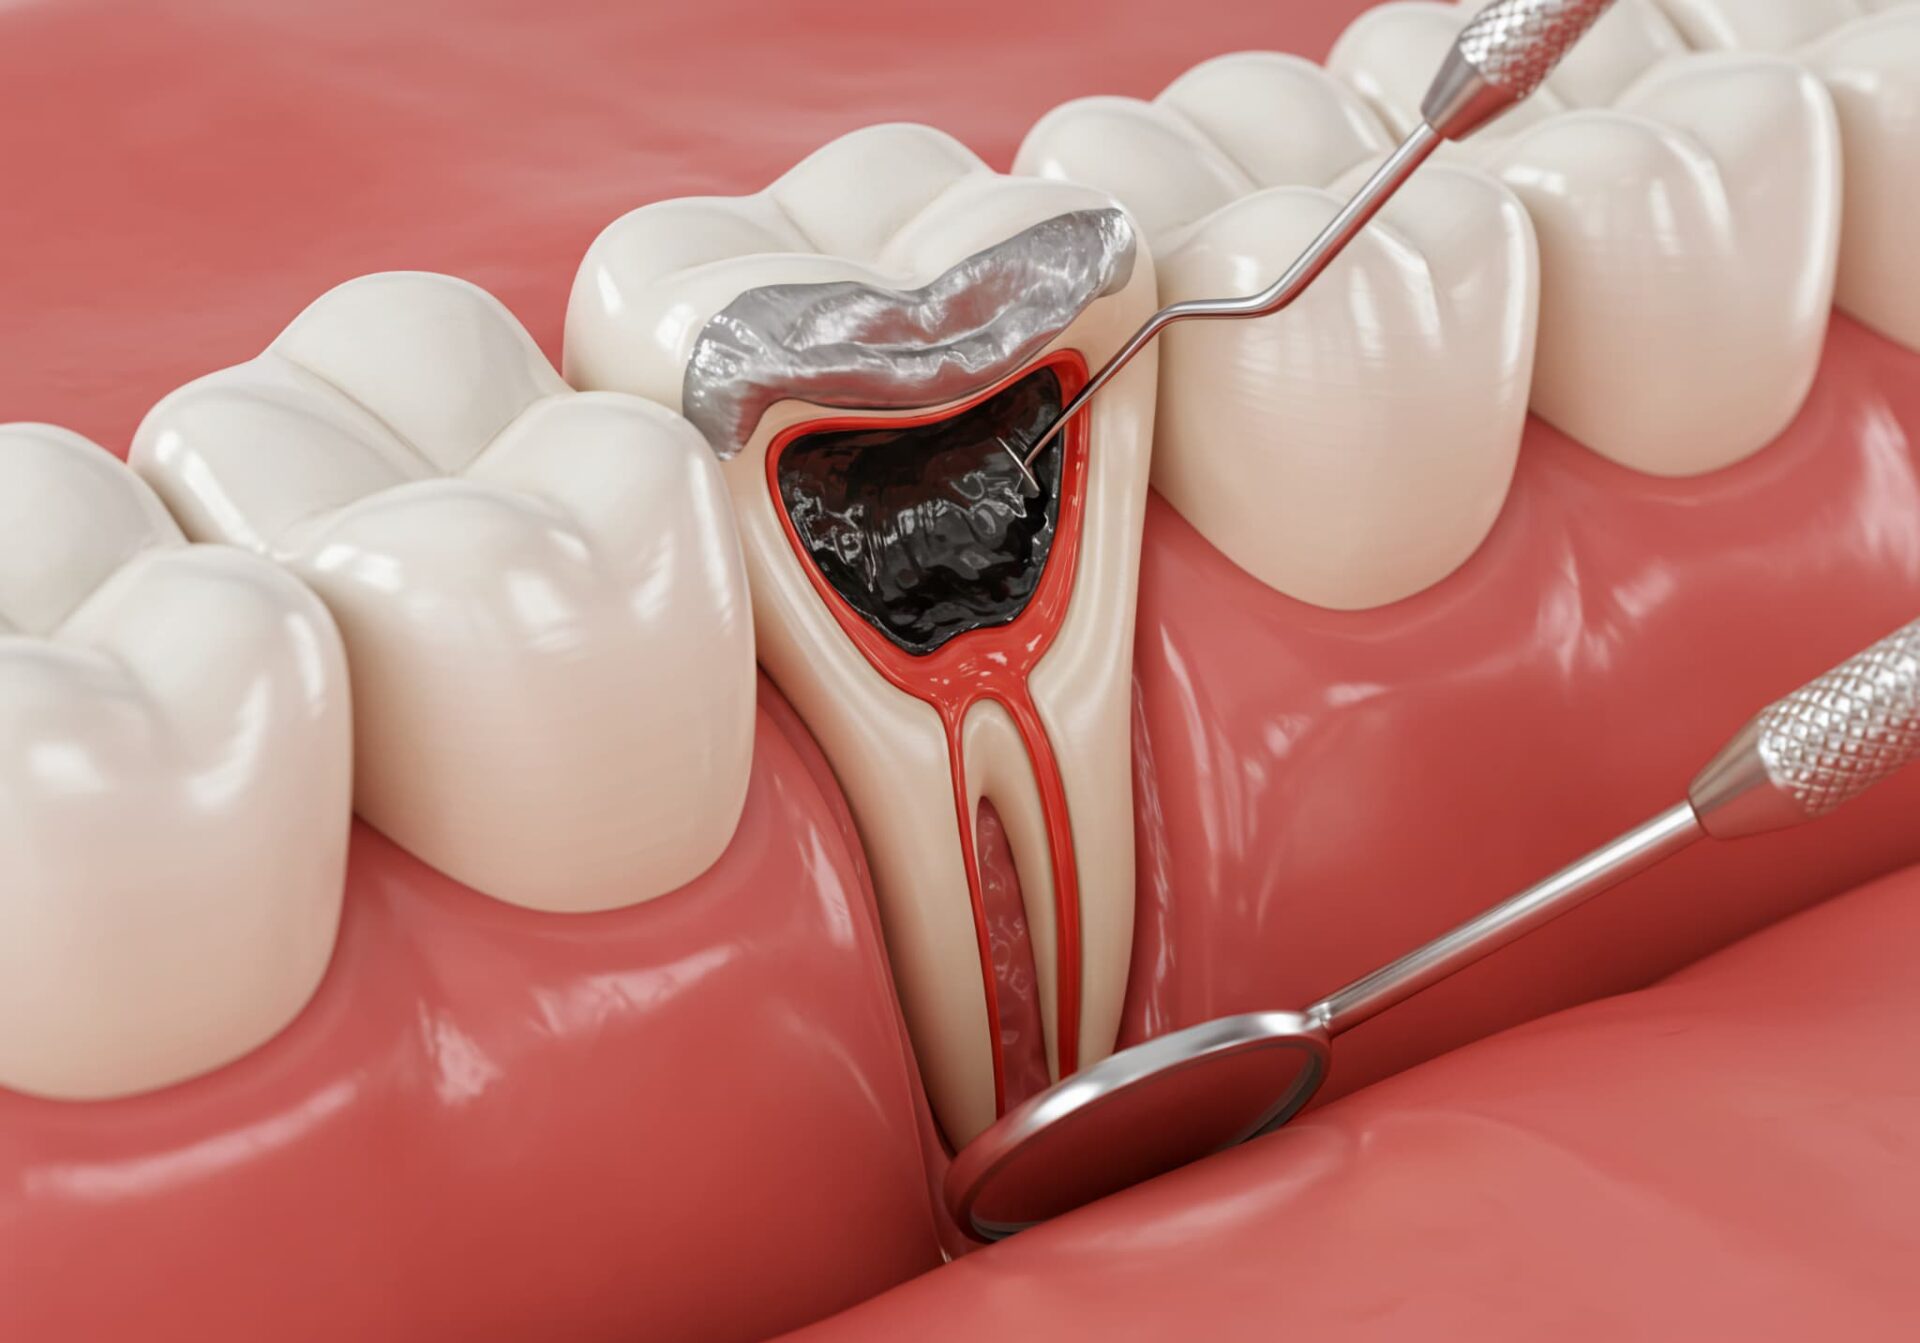

虫歯部分の削除

銀歯を完全に取り外したら、虫歯によって汚染されている歯質を削っていきます。削る範囲は虫歯の進行度や位置によって異なりますが、できる限り健康な歯を残せるように調整します。

必要に応じて根管治療

虫歯が神経や歯根にまで及んでいる場合、根管治療が必要となることがあります。特に、激しい痛みや腫れ、排膿などの症状が見られる場合は、根管内の感染が疑われます。根管治療は、歯を残すことを目的として行われる治療で、感染した組織を除去し、内部を徹底的に清掃・消毒・密封します。